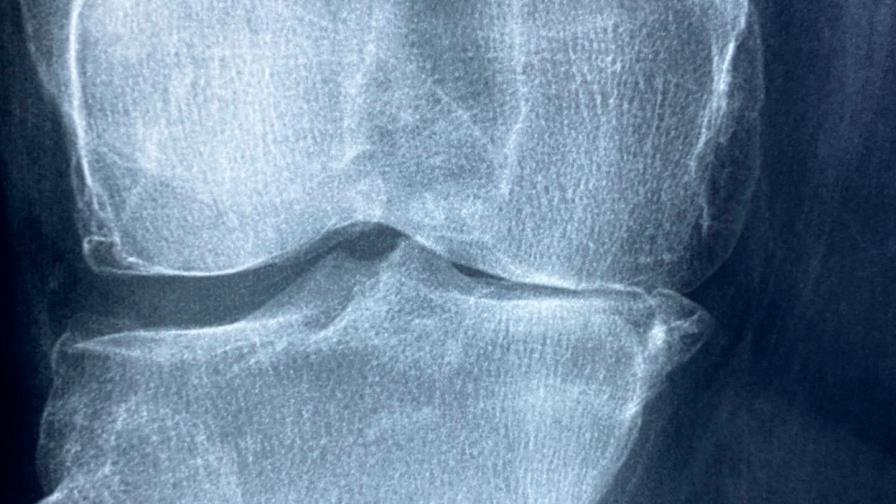

La artritis reumatoide, explica el reumatólogo César Pacheco, es una enfermedad autoinmune e inflamatoria que en Latinoamérica afecta a entre 6 y 8 mujeres por cada varón, y aparece entre los 40 y los 50 años de edad.

Pacheco señala que existen más de 100 tipos diferentes de artritis, pero la reumatoide es de las más comunes.

Pacheco, quien también es presidente del Colegio Mexicano de Reumatología, detalla que esta enfermedad provoca diferentes síntomas, aunque el que más predomina es el dolor.

Sin embargo, con el paso de las semanas, el dolor en las articulaciones, especialmente en las manos, es inminente.

“Eventualmente esas articulaciones se inflaman y limitan el movimiento”, apunta.